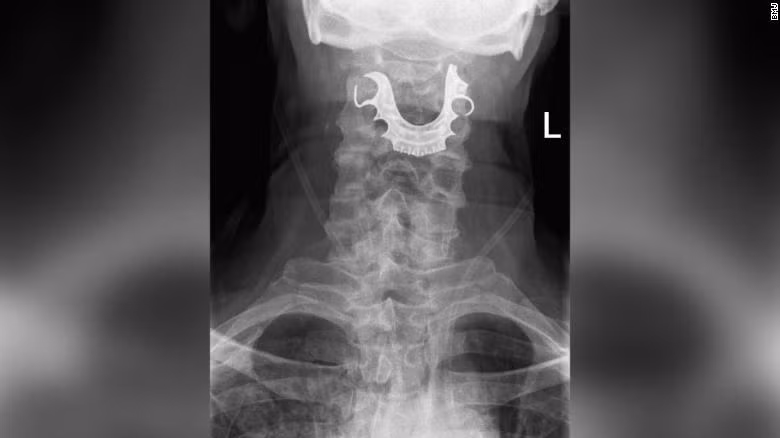

| Hình ảnh hàm răng giả nằm trong thanh quản bệnh nhân |

Tuy nhiên, chỉ 2 ngày sau, tình trạng của người đàn ông ngày một tệ hơn khi không thể nuốt bất kỳ một thứ gì. Sau khi kiểm tra, các bác sĩ đã phát hiện một vật thể hình bán nguyệt nằm ngang thanh quản của người đàn ông, gây sưng tấy bên trong.

Người đàn ông 72 tuổi tiết lộ, răng giả của ông "đã bị mất sau khi nhập viện phẫu thuật” vào 8 ngày trước đó. Ngay sau đó, bệnh nhân đã được tiến hành phẫu thuật khẩn cấp để loại bỏ bộ răng giả và được xuất viện sau 6 ngày.